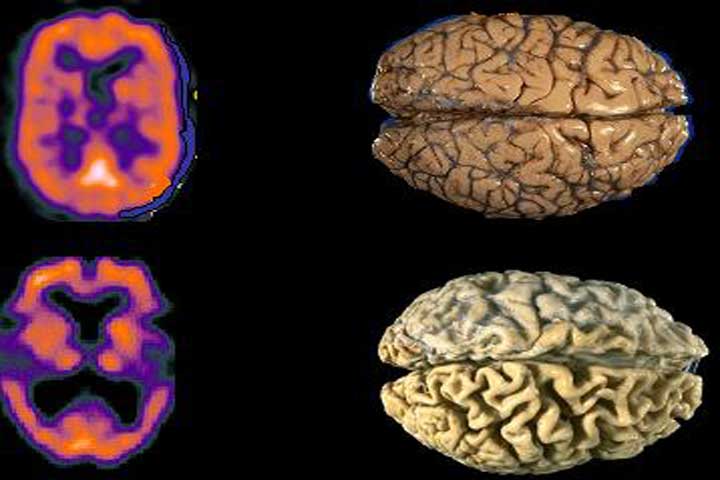

Estudian tratamientos para prevenir enfermedades neurodegenerativas

El Instituto Nacional de Neurología y Neurocirugía "Manuel Velasco Suárez" contribuye con 20 por ciento de líneas de investigación en la prevención y tratamiento de enfermedades neurodegenerativas como Alzheimer, esclerosis múltiple, enfermedad de Huntington y mal de Parkinson. La directora de Investigación Presencial del instituto, María Lucinda Aguirre, destacó que con la atención médica de alta especialidad que ofrece el organ...